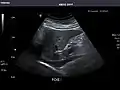

Liver

Liver: Diffusely homogeneous and normal in echogenicity. No focal mass or contour nodularity. No intrahepatic biliary ductal dilatation.